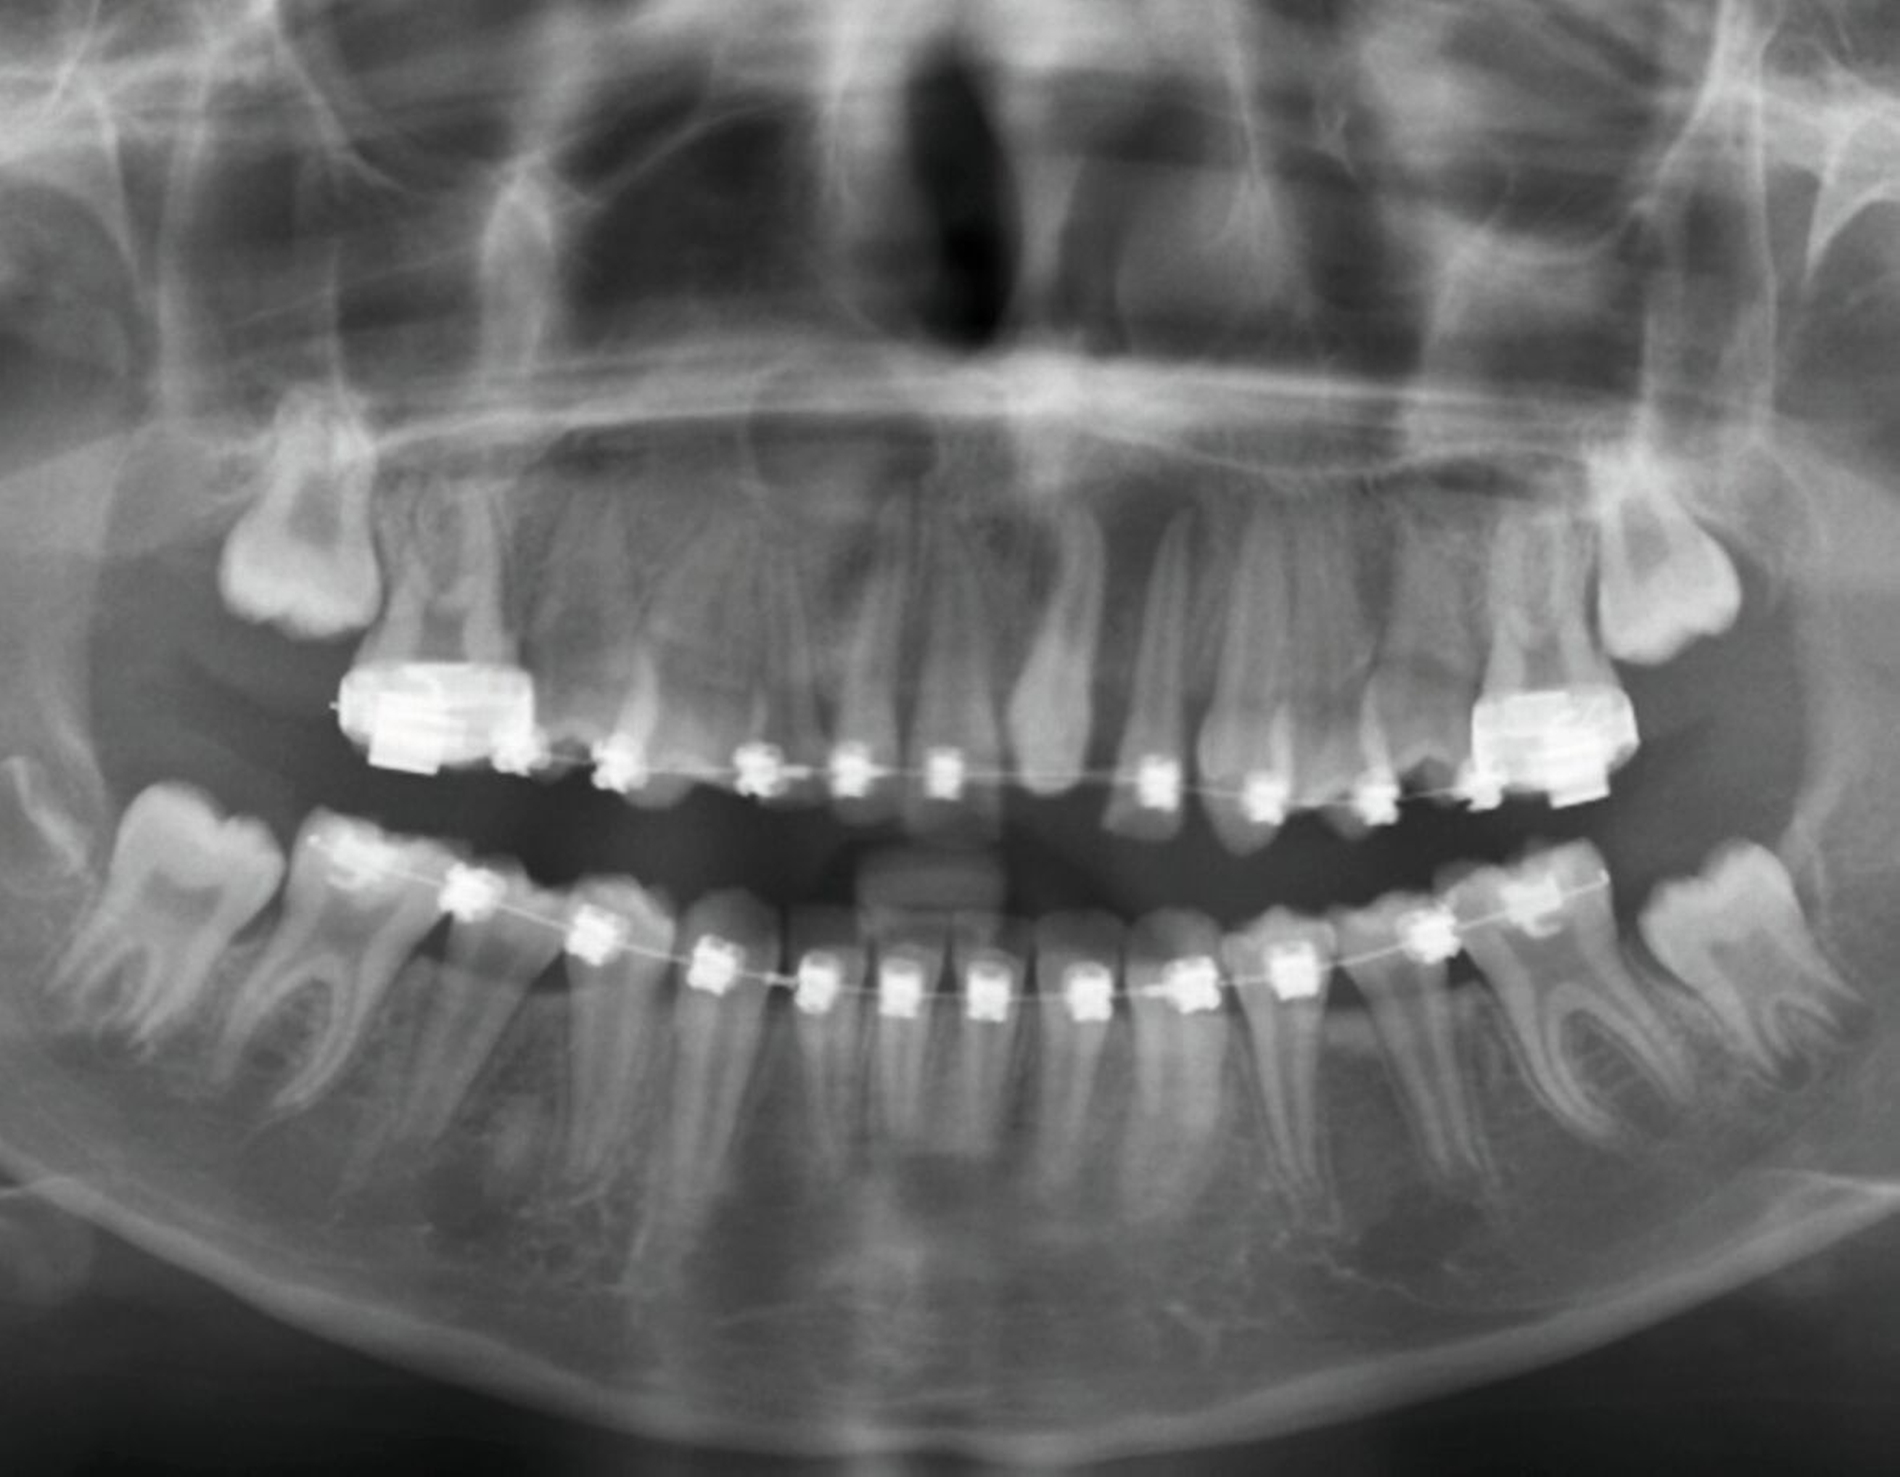

Zwei Jahre nach einem komplexen Zahntrauma mit komplizierter Kronenfraktur 21 und endodontischer Versorgung stellte sich eine elfjährige Patientin mit nun ausgedehnter apikaler Beherdung am Zahn 21 bei uns vor (Abbildung 1). In ihrer Krankengeschichte hatte die Patientin im Alter von vier Jahren eine Leukämie überwunden. Es wurden keine weiteren gesundheitlichen Probleme angegeben. Im OPG zeigt der Zahn 21 eine periapikale Aufhellung im Sinne einer Parodontitis apicalis chronica mit nun akuten klinischen Schmerzen (Abbildung 1).

Zur weiteren Abklärung wurde eine dreidimensionale Aufnahme durchgeführt (DVT). Dabei bestätigte sich die erhebliche Osteolysezone im apikalen Bereich des vormals traumatisierten Zahnes 21. Der Zahn 13 stellt sich hoch verlagert am Nasenboden dar, während es bei dem persistierenden Milchzahn 53 zu einem natürlichen Lückenschluss in regio 13 gekommen ist (Abbildung 2).